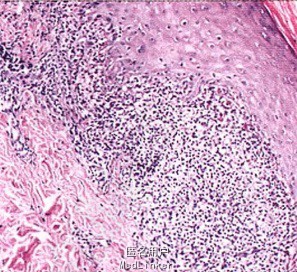

皮肤科检查:皮疹泛发,以双上肢、胸腹部、背部为主,皮损表现为米粒至绿豆大小暗红色丘疹,部分融合倾向,可见同形反应。甲、唇及口腔黏膜未见损害。腹部皮损组织病理:表皮角化过度,颗粒层呈楔形增厚,棘层增厚,基底细胞液化变性,真皮浅层单一核细胞为主的炎症细胞呈带状分布。

诊断:泛发性扁平苔藓。治疗:局部外用糖皮质激素药膏,

随访中。扁平苔藓临床表现的类型多种多样,但所有类型的组织病理学表现都相同。典对任何类型的扁平苔藓治疗前,都应除外药物引起的可能性。目前局部外用糖皮质激素仍是治疗扁平苔藓的主要方法。